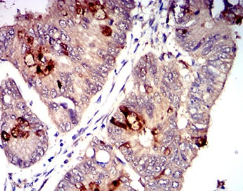

CD1C Mouse Monoclonal antibody[3G1B3]

IHC    1/200 - 1/1000